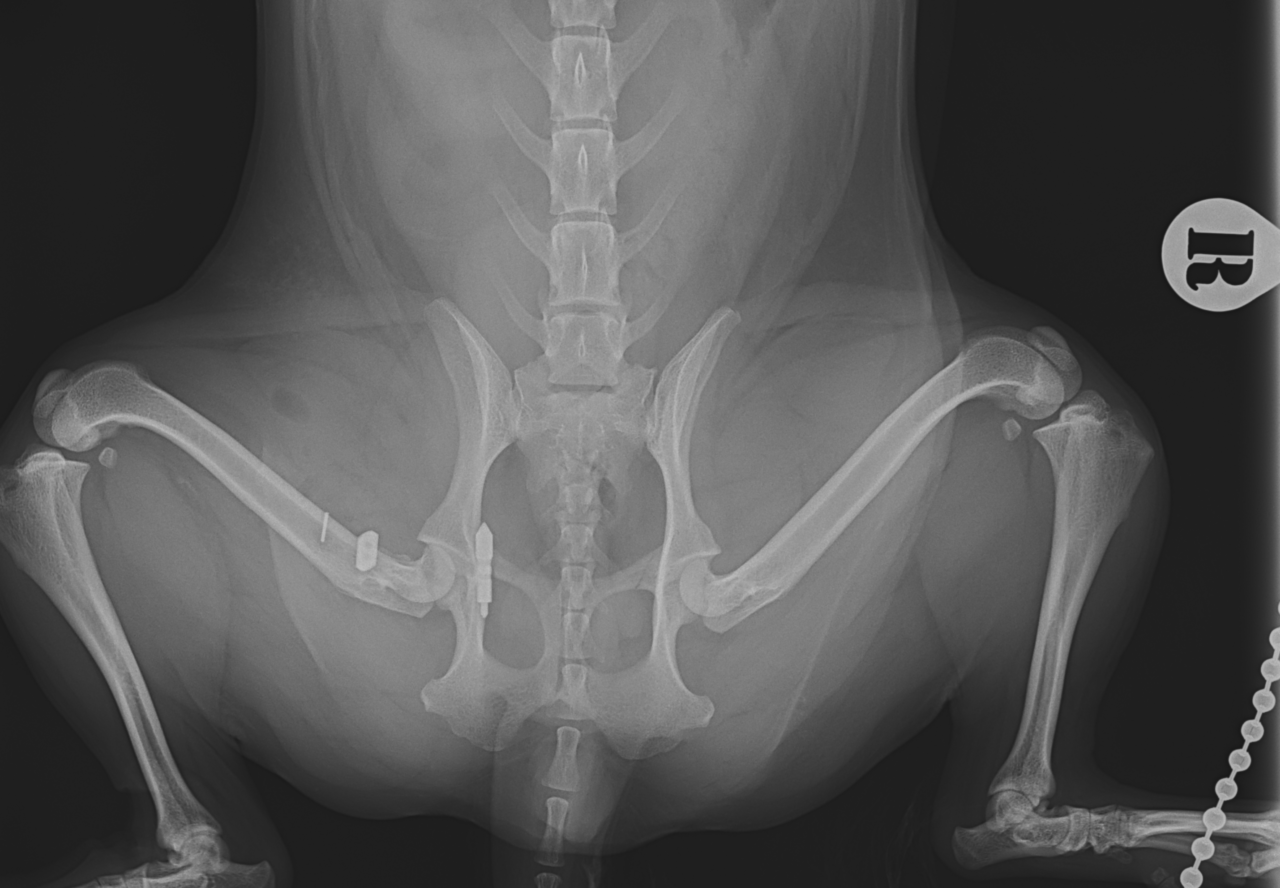

輪禍外傷による股関節脱臼の患者さんに対してBullet–Shaped Toggle Rod (BUSTOR)で整復を行いました。本症例は恥骨の骨折も併発していたため、CTで寛骨臼の評価も実施しました。低侵襲かつ短時間で整復が可能です。しばらくは安静が必要です。